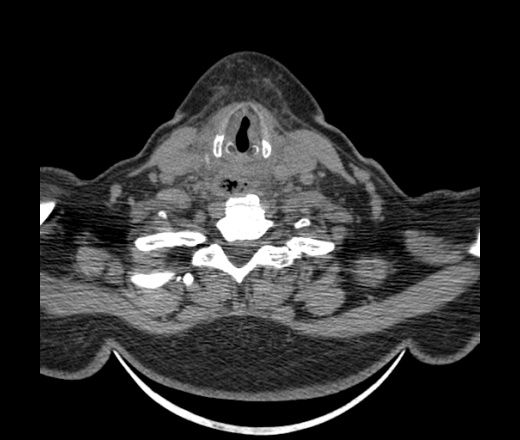

Женщина поступила в х/о спустя 4 дня после того как при употреблении карася подавилась костью.

Наличие газа в средостении на протяжении тел С2-С6 (медиастинальна эмфизема); рыбная кость на уровне тела С6.

При всем уважении, но говорить о медиастинальной эмфиземе, оценивая мягкие ткани шеи, как-то слишком резко. На мой взгляд, это ретрофарингеальное пространство.

Эвакуировали почти 100мл гноя. Но кость не смогли найти. Думаю что она даст дальнейшее ослоднение. Эндоскопически за черпалонадгортаной звязкой не смогли зайти в пищевод, все мягкие ткани отечные, просвет пищевода сдавлен. По всей видимости параэзофагеальная клетчака тоже задействована. Эмпиема, если ее можно так назвать, незнаю как правильно дошла до уровня яремной вырезки. Чем закончиться напишу. Ждем медиастинита.

Согласен с Вами; конечно, наличие газа в клетчатке ретрофарингеального пространства (затмение с опечаткой..). К сожалению, процесс "продвигается" к медиастиниту. Но почему никто, не отмечает наличие рыб. кости; или это для Всех очевидно?

Кость то мы сразу выявили, размеры где то 17*2мм, но ее так и не получается найти в этой каше